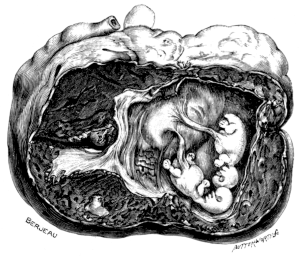

| 23. | A Gravid Uterus in Sagittal Section | 79 |